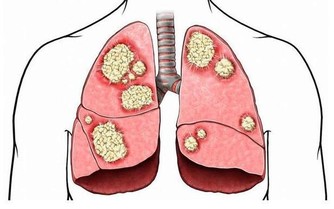

2、各種骨骼疾病

鈣缺乏很容易導致骨骼疾病和兒童。如果缺鈣會導致佝僂病,雞胸,缺鈣的孩子會出現生長痛,如果成人缺鈣會導致腰酸背痛、骨質增生。退行性病變,老年人缺鈣就會導致骨質疏鬆,容易骨折。很多老年人因為缺鈣,50以上就會出現駝背,還有一些人因為缺鈣,導致股骨頭壞死。